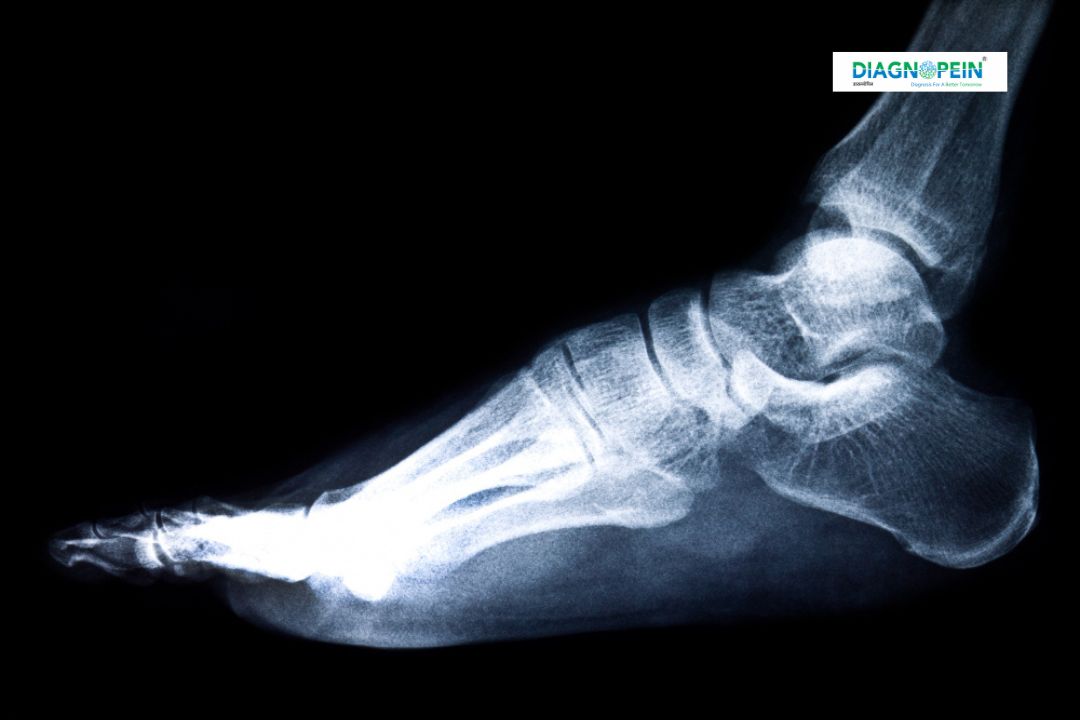

The X-Ray Foot AP View (Anteroposterior view) is a specialized diagnostic imaging test that provides a clear front-to-back picture of the bones and joints in the foot. At Diagnopein Nashik, we use advanced digital X-ray technology to produce high-quality images that help orthopedic specialists, radiologists, and physicians detect bone injuries, fractures, arthritis, deformities, and other foot abnormalities with precision.

The X-Ray Foot AP View plays a crucial role in diagnosing both acute and chronic foot conditions. It allows for a complete visualization of the tarsal, metatarsal, and phalangeal bones.